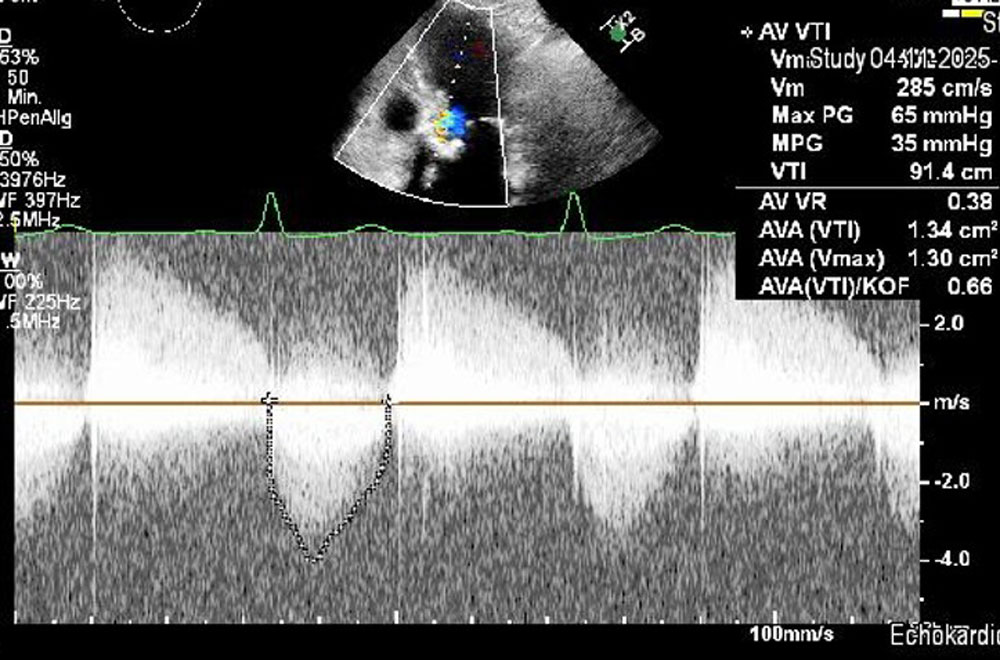

mittelschwere bis schwere Aortenklappeninsuffizienz

mittelschwere Aortenklappenstenose